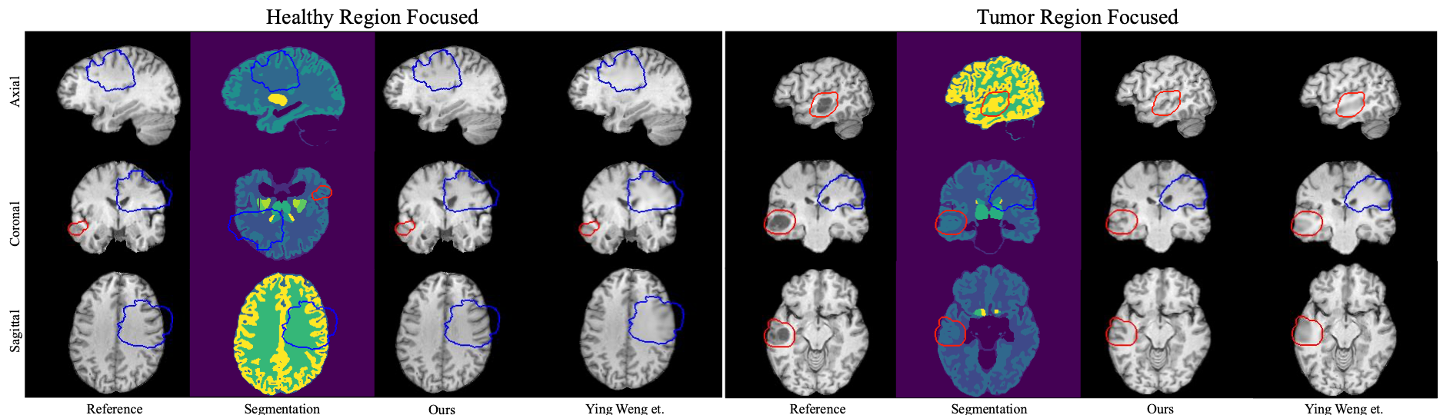

For the BraTS 2025 Inpainting Challenge, we developed PSegGAN (Pseudo-Segmentation-Guided GAN), a 3D inpainting framework that integrated anatomical priors directly into the generative process rather than treating inpainting as a generic pixel completion task. We guided reconstruction using pseudo-segmentation signals to enforce tissue-level consistency and structural continuity, enabling the model to recover plausible neuroanatomy beyond surface-level realism. This approach achieved 🥈 2nd place globally, demonstrating high-fidelity reconstruction with strong anatomical validity under large missing-region scenarios.